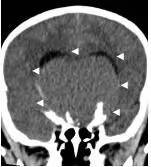

病例1:患儿男性,9岁。因反复出现意识丧失、视力降落半年收入院。入院后CT及 MRI显示颅内有形态不规则、“超大型”的颅咽管瘤,最大径约10厘米,见图1、图2。

图1.术前CT显示典型的囊性颅咽管瘤

白色三角显示肿瘤边界

患儿入院后第三天,病情恶化,意识不清,急诊行肿瘤囊穿刺引流术,引流出囊液约200毫升,引流后患儿精神立即好转,肿瘤体积减小,引流手术切口设计及引流后CT见图7、图8。调养7天后在全麻下行开颅手术切除肿瘤,经过10个小时的努力,完全切除肿瘤,术后患儿清醒,语言交流正常,左侧上下肢肌力稍弱。患儿经历一系列的并发症,如电解质紊乱、脑水肿、癫痫发作等,共计住院47天后出院。术后CT见图9。